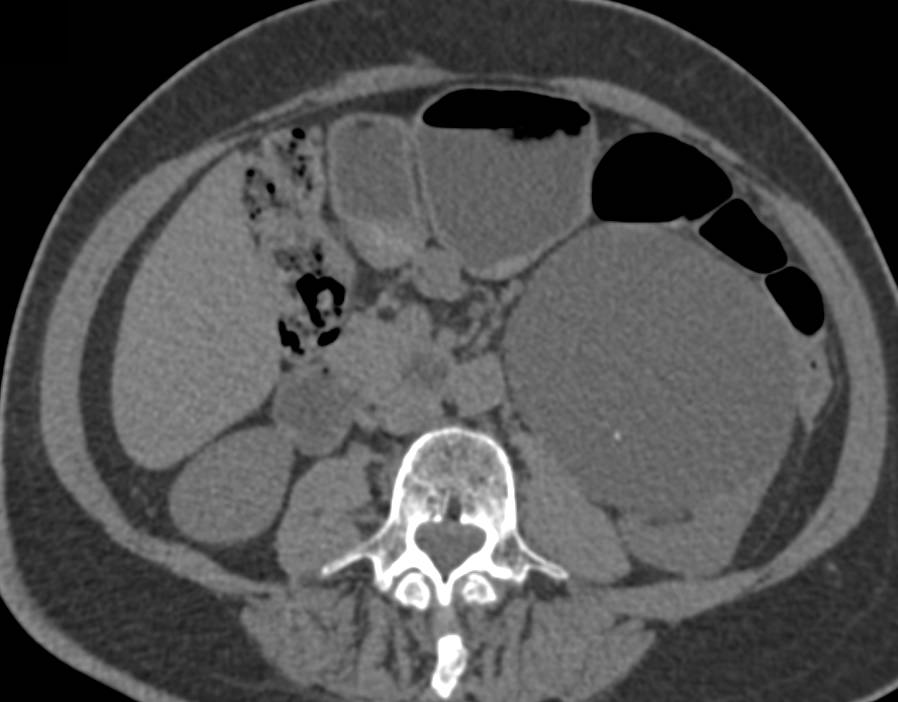

Subtle Carcinoma Left Kidney